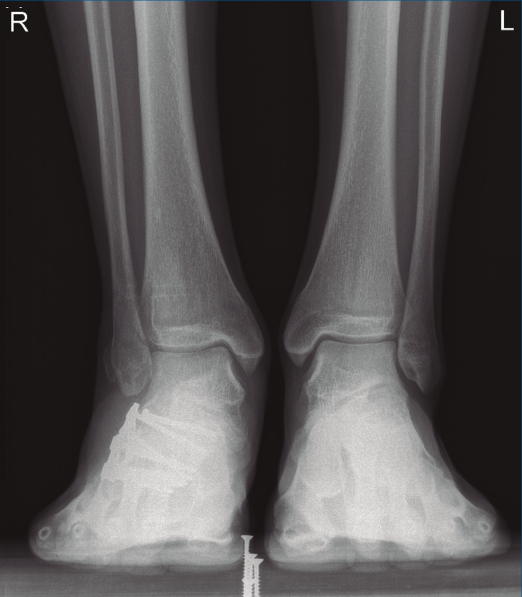

A los 9 meses únicamente presentó dolor ocasional al nivel de la articulación subastragalina y molestias en la planta del pie al deambular descalzo, por lo que se pauta plantilla amortiguadora, con la que mejora notablemente la sintomatología. Presentó una puntuación de 83 sobre 100 en la escala de la American Orthopaedic Foot and Ankle Society (AOFAS), ligeramente superior a la media descrita en estudios previos(2,3). Radiográficamente se evidenció una anatomía restablecida del calcáneo y de la sindesmosis, así como una altura adecuada de ambos tobillos (Figuras 12 y 13). Dada la buena evolución, se decidió continuar con el seguimiento anual del paciente sin realizar la extracción del material de osteosíntesis, para valorar la necesidad de una futura artrodesis subastragalina.

Figura 1. Luxación del astrágalo en mortaja tibioperonea, fractura maléolo peroneo y espacio subperoneo ocupado por calcáneo.

Figura 8. Radiografía anteroposterior de tobillo, inclinación lateral del astrágalo, ocupación del espacio subperoneo, fractura maléolo peroneo y apertura de sindesmosis.